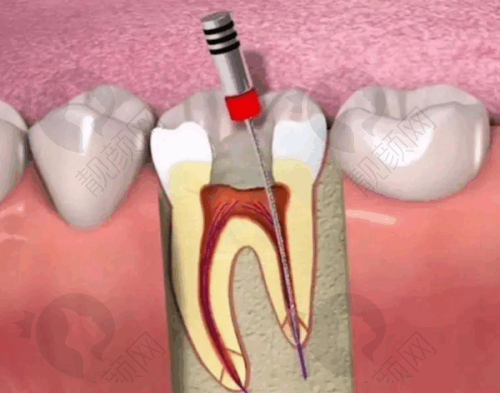

大家都知道,根管治疗是治疗牙髓炎、根尖周炎等牙齿疾病的有效方法,但不同医院的价格差异可能比较大。乌鲁木齐福宏林口腔根管治疗 399 元起,这个价格在市场上是相当有竞争力的。

不过呢,这个 399 元起并不是说所有的根管治疗都是这个价。实际的价格会根据牙齿的具体情况有所不同。比如前牙的根管治疗相对简单,价格可能就比较接近 399 元这个起步价;而后牙的根管系统比较复杂,治疗难度大,价格可能就会高一些。

首先,医院的技术实力特别强。医生们都经过专精的培训和丰富的临床实践,对于根管治疗的各个环节都非常熟练。他们采用精良的根管治疗技术和设备,能够正确地找到根管的位置,完全清除根管内的感染物质,确保治疗的成效。